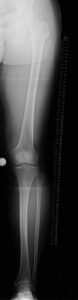

変形性膝関節症として治療を受けていた特発性大腿骨内顆骨壊死

00134306_20240910_CR_0000_00